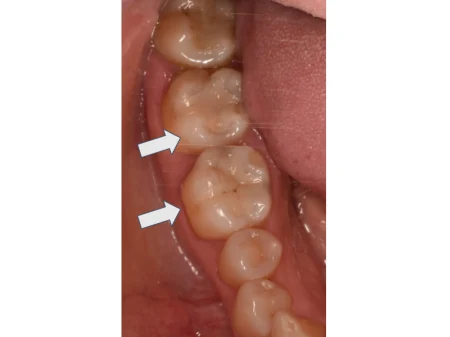

治療後

| カウンセリング・診断結果 | 拝見したところ、右下の奥歯2本(第1大臼歯/6番、第2大臼歯/7番)にゴールドの詰め物が入っており、口を開けた時にやや目立つ印象でした。 |

| 行ったご提案・治療内容 | 患者様のご希望に沿って、ゴールドの詰め物を外してから型を取り、白い詰め物を作製して歯を修復する治療を行いました。 新しい詰め物の種類は、目立ちにくい白さで適度な強度もあるセラミックの「E-maxインレー」をご提案しました。 セラミックは歯によく馴染んで見た目が良く、虫歯にもなりにくいことを丁寧にご説明したところ、同意いただきました。 |

| 術後の経過・現在の様子 | ご自身の歯に馴染んだ見た目になりました。噛み合わせも問題ありません。 患者様にも「口を開けた時に気にならなくなり嬉しい。食事もしっかり噛めている」と大変ご満足いただきました。 治療した歯を長くお使いいただけるよう、現在は定期的なメンテナンスでご来院いただいています。 |